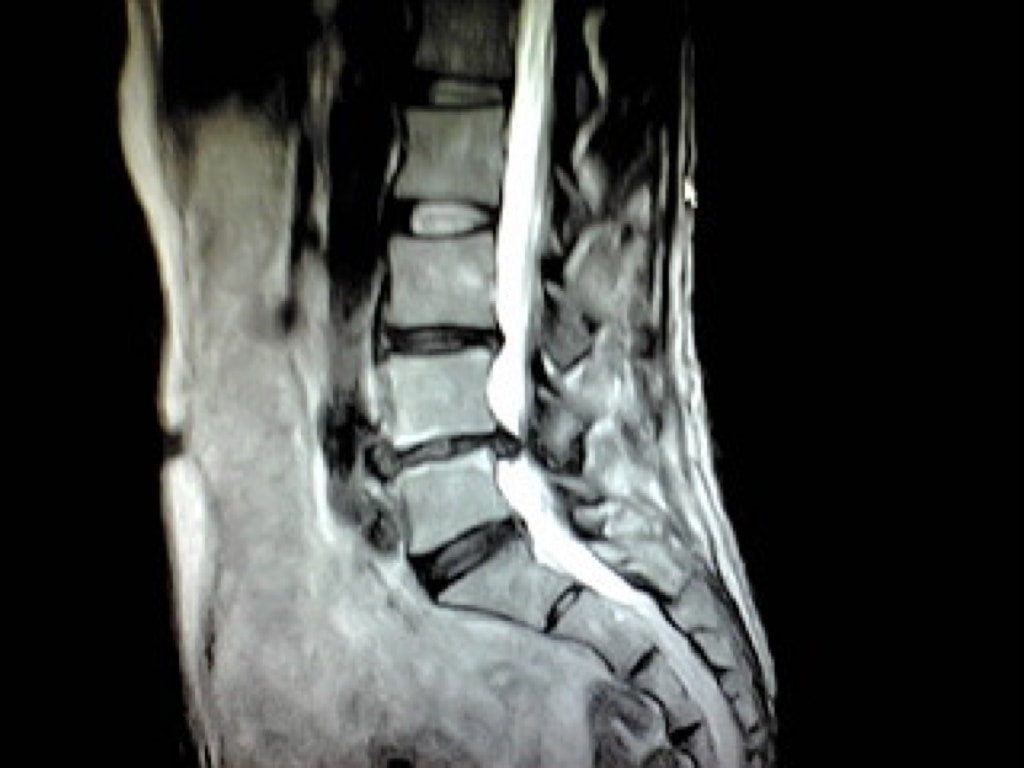

MRIドックのご案内

当クリニックでは脳神経外科領域の診療の他にMRIを用いた様々な検診メニューをご用意いたしました。『病状はなく病院へ行くほどではないけれど何か気になる』『ご自身の体の状態を正確に知りたい』などの場合にお役に立てる事と存じます。

病気の早期発見のために、最新のMRIを用いた本格的な検診。

大病院などで用いられている最新のMRIを使用し、精度の高い結果を得、かつ痛みや不快感を極力排除することを可能にしました。

検査画像は、豊富な経験を持つ専門性の高い読影医が担当し、読みやすく質の高いレポートとしてご提供します。また、ご要望に応じて、医師の説明を受けながら、自分の目で検査の画像を確認し、現在の健康の状態を理解して頂くことも出来ます。